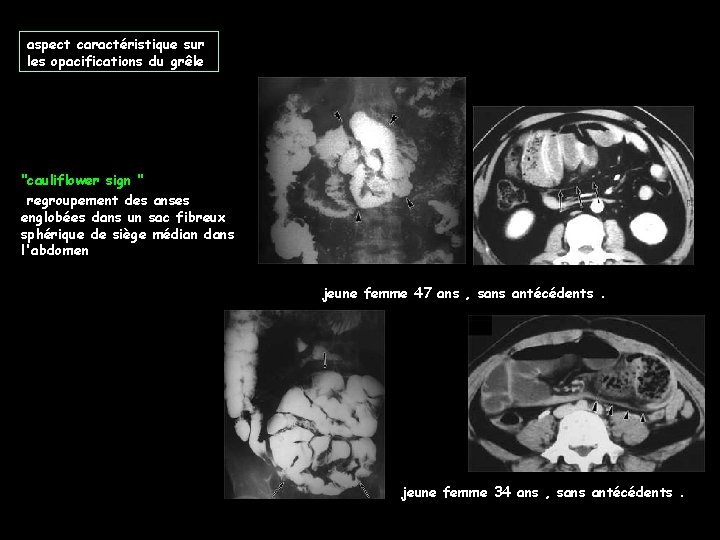

aspect caractéristique sur les opacifications du grêle "cauliflower sign " regroupement des anses englobées dans un sac fibreux sphérique de siège médian dans l'abdomen jeune femme 47 ans , sans antécédents. jeune femme 34 ans , sans antécédents.

sémiologie scanographique de la péritonite sclérosante encapsulante (abdominal cocoon) -épaississement du péritoine viscéral généralement diffus ; plus rarement nodulaire , formant un "sac" autour de la presque totalité des anses grêles -calcifications péritonéales fines et diffuses ou conglomérées ; ce sont elles qui ont valu le nom d'abdominal cocoon à la péritonite fibrosante encapsulante -rehaussement du péritoine plus marqué que dans les péritonites bactériennes -collections liquides localisées et rétraction intestinomésentérique qui positionne les anses grêles en arrière des collections et en situation médiane dans l'abdomen -épaississement et calcification des parois des anses grêles -calcifications des capsules du foie et de la rate